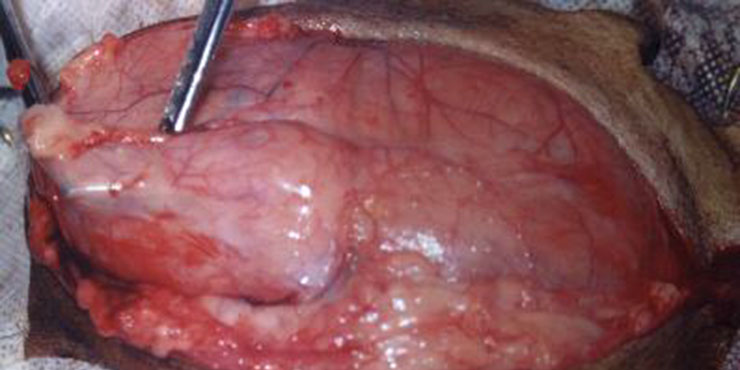

Hérnia inguinal com útero em seu conteúdo.

Corno Uterino

Exposição do corno uterino direito, ovário, trompa e parte do útero.